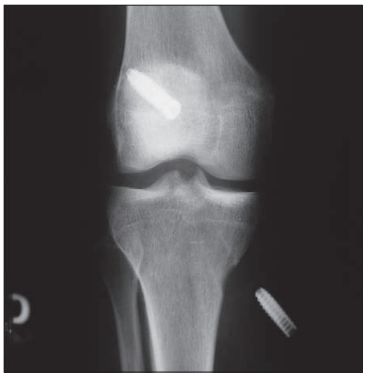

Migracja piszczelowej śruby interferencyjnej po rekonstrukcji ACL

Wystawanie śruby piszczelowej ponad warstwę korową kości

/ 2Przemieszczenie śruby poza kanał kostny

Migracja śruby piszczelowej poza kanał kostny